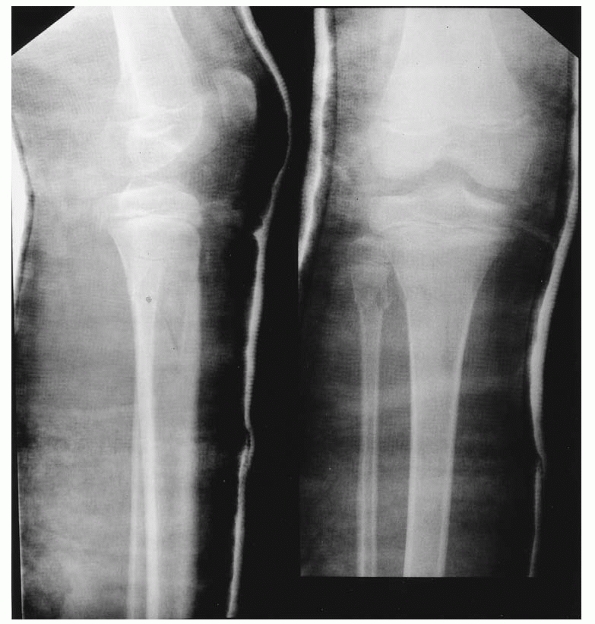

![]() |

|

FIGURE 25-3

Anteroposterior radiographs of the knee in a 9-month-old child who was abused show a proximal tibial metaphyseal corner fracture with extension into the physis (right). The follow-up radiograph on the left demonstrates marked new bone function, which suggests the degree of periosteal stripping that occurred at the time of the injury. |